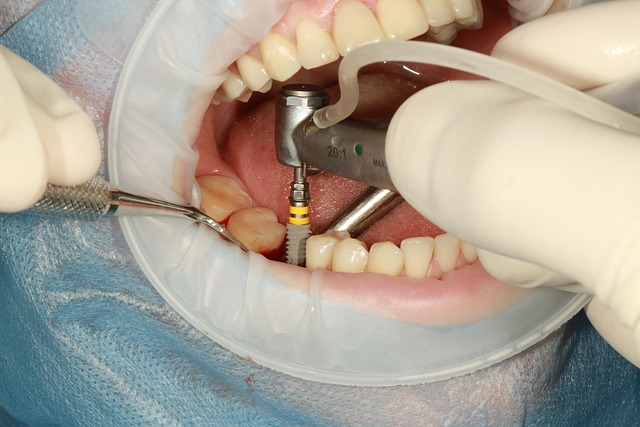

2) 식립 수술(당일)

국소마취 하에 인공치근을 심는 핵심 시술 단계입니다. 보통 30~60분이며, 당일 귀가가 가능하나 수술 당일·익일에는 운동과 음주를 피하고 냉찜질로 관리하면 이후 과정과 전체 임플란트 시술기간에 긍정적입니다.